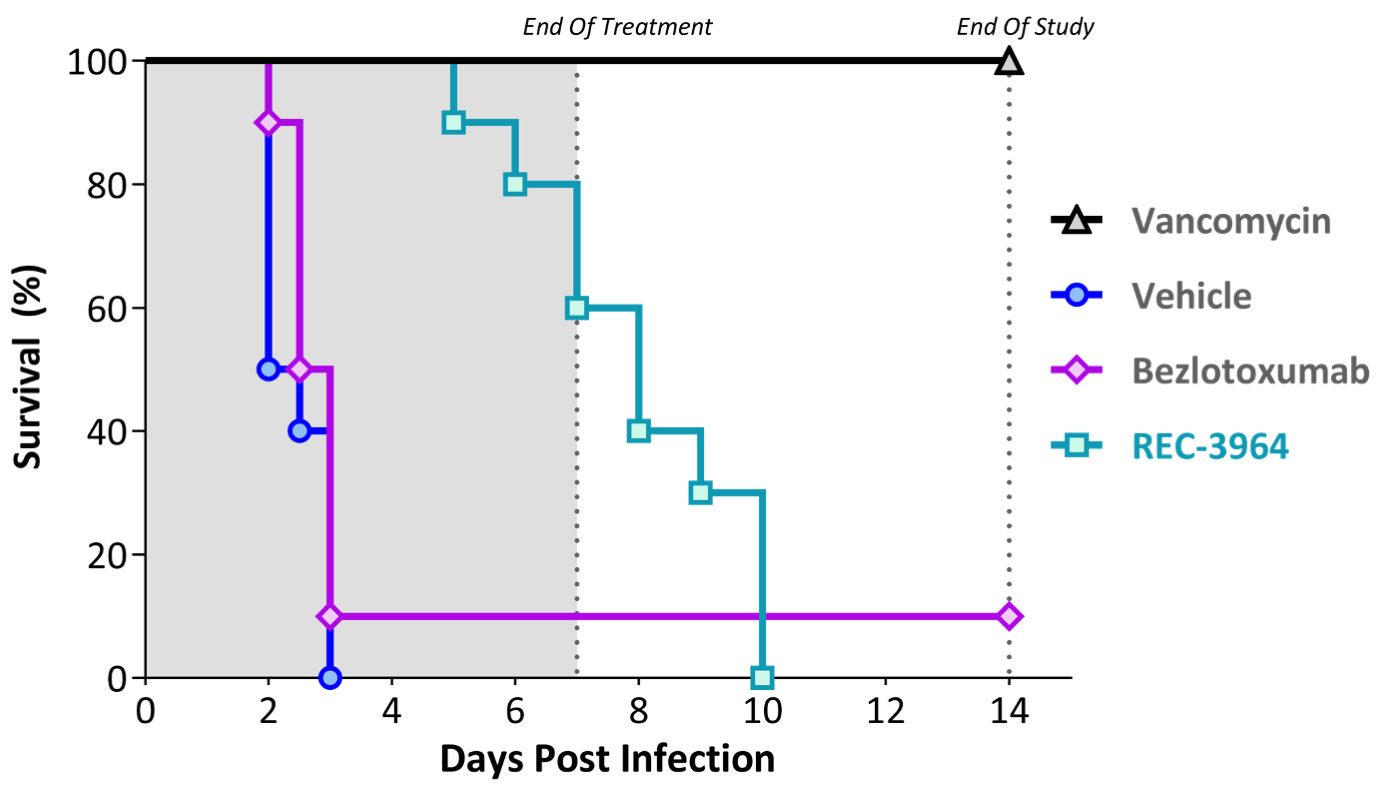

•Completed a Phase 1 study for REC-3964 in healthy volunteers for the potential treatment of Clostridioides difficile (C. difficile) infection with a favorable safety and tolerability profile